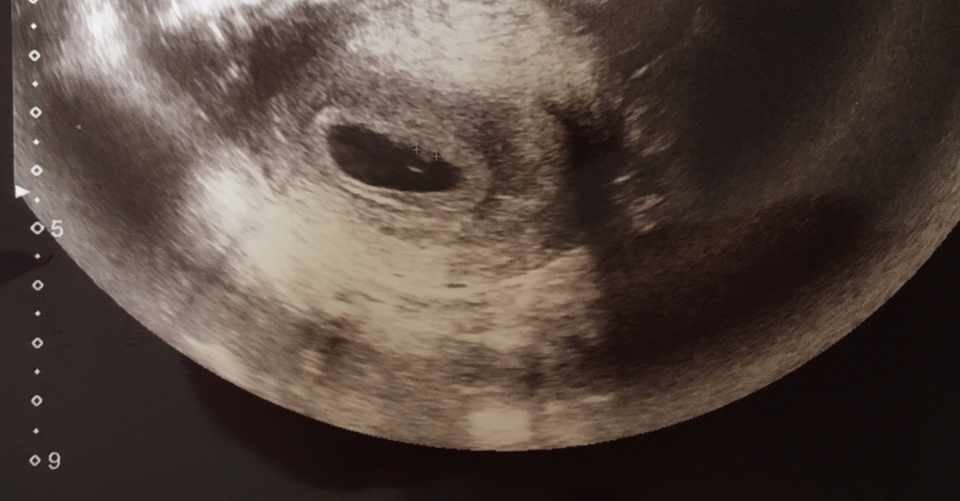

妊娠6週4日 6w4d の超音波 エコー 写真

心拍確認 妊娠2ヶ月 6週4日 の写真 ベビカム成長記録 妊娠 出産 育児に関する総合情報サイト ベビカム

6 週 4 日の年齢で胎児の超音波画像 の写真素材 画像素材 Image

妊娠6週4日胎のう1 35 綺麗な丸型今日 残念ながら赤ちゃんがエコーに Yahoo 知恵袋